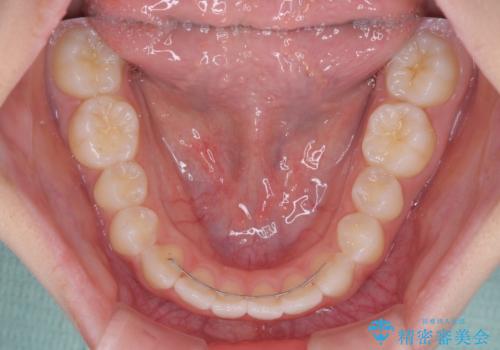

- 前歯のデコボコを気にして来院された高校生の患者様です。

捻れた前歯が前方に飛び出している点も気になっており、目立たない装置を希望されたため、インビザラインを用いて矯正治療を行うこととしました。

上下ともに少し捻れが残っていたため、治療の継続を提案しましたが、本人も親御さんも満足とのことで、治療を終えました。

捻れの改善により突出感も改善されました。